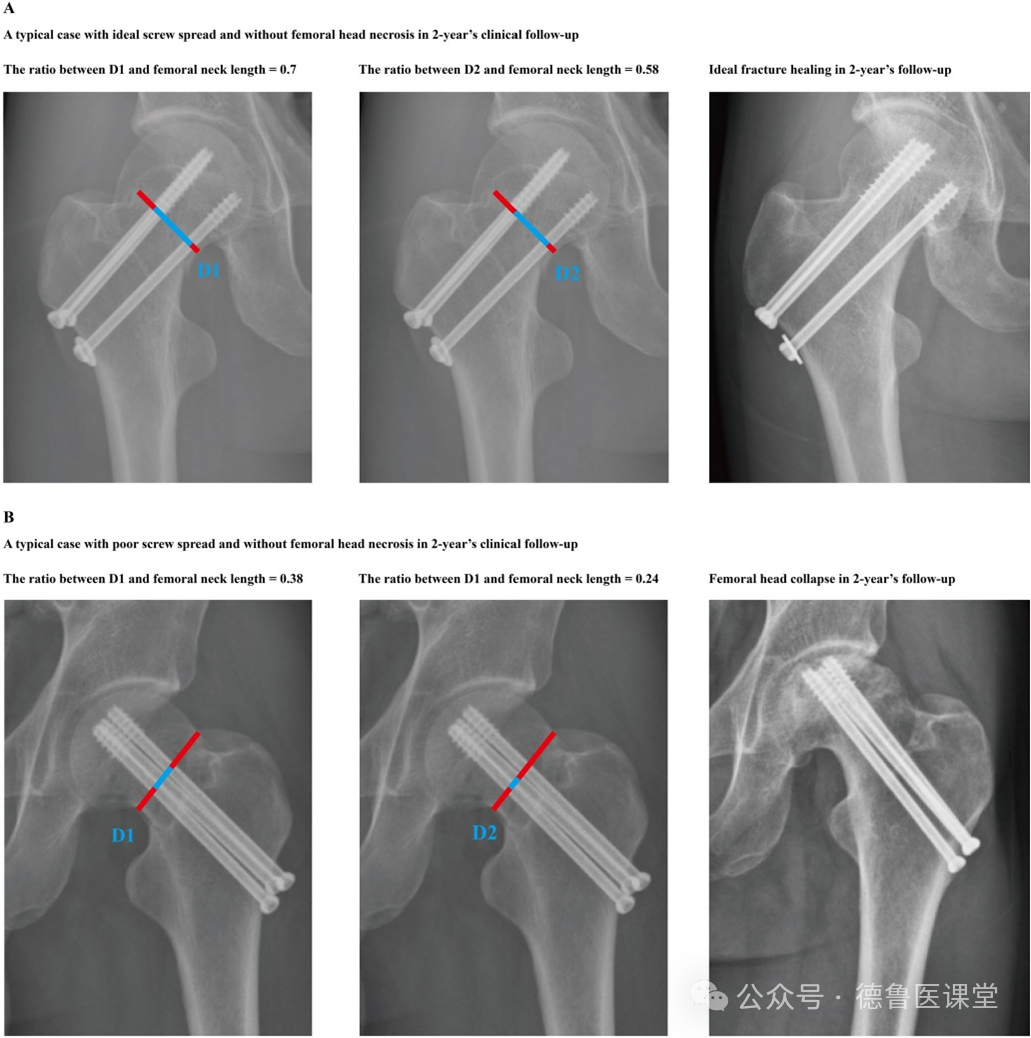

Na Figura A, os parafusos estão distribuídos de forma ideal, com consolidação óssea alcançada; na Figura B, os parafusos estão mal distribuídos, resultando em necrose da cabeça do fêmur.

Este estudo envolveu uma revisão abrangente de dados de imagem de pacientes com fraturas do colo femoral. Foi medida a distância máxima entre os parafusos cranial e caudal ao longo da linha de junção entre a cabeça e o colo do fêmur. Essa medida foi então dividida pelo comprimento do colo femoral para calcular o grau de distribuição dos parafusos. As diferenças neste parâmetro foram analisadas estatisticamente entre pacientes com e sem necrose da cabeça femoral. A análise de regressão foi utilizada para identificar possíveis fatores de risco para necrose da cabeça femoral. Além disso, as implicações biomecânicas das variações no grau de distribuição dos parafusos foram simuladas utilizando modelos numéricos tridimensionais.

A revisão clínica indicou que pacientes com necrose da cabeça do fêmur apresentaram classificações subótimas na distribuição dos parafusos, as quais foram identificadas como um fator de risco independente para maior probabilidade de desenvolver necrose da cabeça do fêmur. Além disso, constatou-se que a estabilidade da fixação melhora com a otimização da classificação da distribuição dos parafusos.